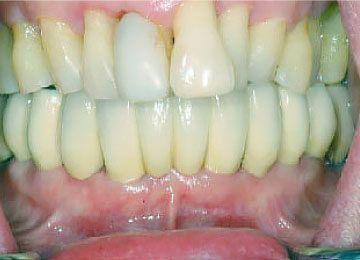

Имплантация зубов: фото «До» и «После»

Фото ДО

Фото ПОСЛЕ

Наведите для просмотра

All-on-4